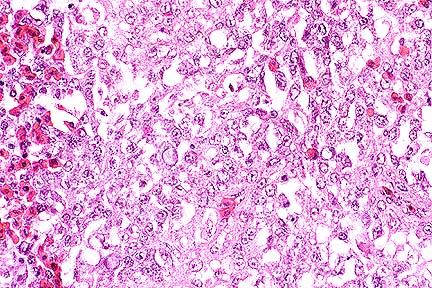

Carmininophilic yeasts in the cerebrum of a horse. The clear "halo" around each yeast is due to shrinkage of the capsule during fixation. (Mucicarmine, 400X, 40K)

Conference Note: Cryptococcus neoformans is a yeast-like fungus in tissue. It reproduces by single buds, is 4-8 æm in diameter, and is surrounded by a thick mucopolysaccharide capsule. The capsule stains well with mucicarmine and alcian blue and is PAS-positive. Cryptococcosis occurs worldwide; the source of the infection is believed to be soil, especially in areas contaminated by pigeon or other bird feces. All species of animals can be affected, but cats are affected more often than other domestic animals.

Histologically, the lesion is described as having a "soap-bubble" appearance, the result of the thick, nonstaining, capsule. The inflammatory response to cryptococcosis is usually minimal, consisting of macrophages, lymphocytes, and plasma cells. Occasionally, a granulomatous reaction will develop, especially in the lungs.